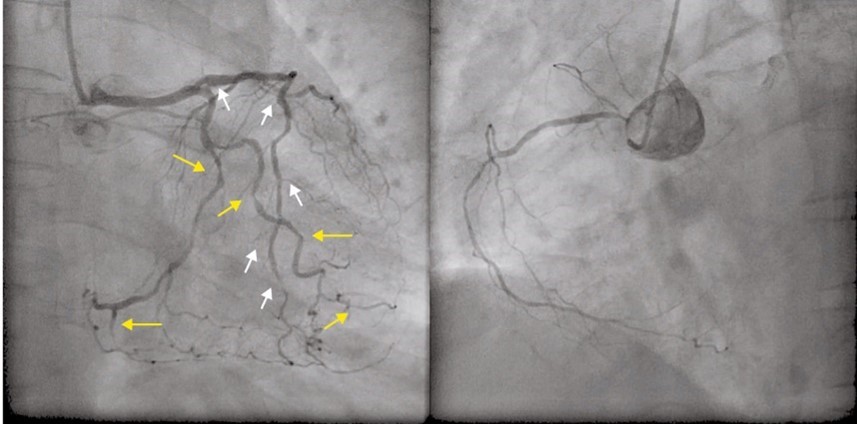

Typiskt på angiografi vid T2D?

Spindelben vid angiografi